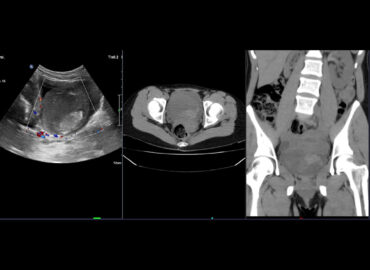

Paciente sexo femenino de 39 años con lumbalgia y hematuria